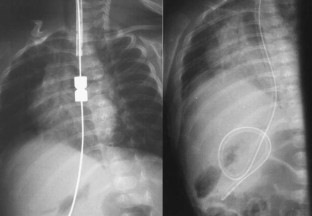

Between September 2001 and March 2004, five children were selected for treatment. Two of the children had esophageal atresia without fistula (type A) and three had atresia with fistula converted to type A surgically; however, surgeons failed to achieve an anastomosis because of the width of the gap. Neodymium-iron-boron magnets were used. Daily chest radiographs were taken until union of the magnets was observed. They were then replaced with an orogastric tube.

Anastomosis was achieved in all patients in an average of 4.8 days. One patient, with signs of early sepsis, was successfully treated with antibiotics. In four of the five patients, esophageal stenosis developed. At the time of this report, two patients were free of treatment and on an oral diet (after 26 months), two patients required periodic balloon dilatation, and one patient had recently undergone surgery due to recurrent esophageal stenosis not amenable to balloon dilatation.

Fig. 4